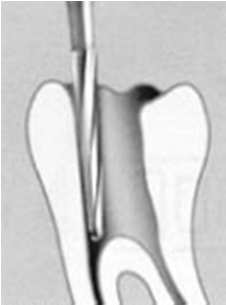

La apertura consiste en llegar a descubrir el techo de la cámara pulpar. Lo puede hacer con alta velocidad con una fresa o punta de diamante con abundante refrigeración acuosa.  Le aconsejamos que la apertura la realice con aislación relativa. Ver imagen izquierda.

La sensación al llegar a la cámara pulpar "es de caer en un vacío" ahí debe terminar la apertura propiamente dicha y debe pasar al proceso de rectificación de la cámara para el acceso a los conductos.